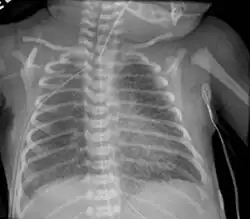

| Chest radiography showing severe pulmonary interstitial emphysema | |

A chest X ray may show a "salt and pepper" appearance due to the linear lucencies that are present.